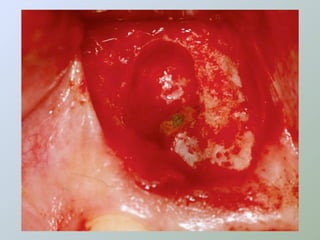

CURETAGEM

O tecido inflamatório em torno do

ápice radicular deve ser removido

para:

• Ganhar acesso e melhorar a

visibilidade

• Obter material para histopatológico

• Reduzir a hemorragia

• Evitar danos aos dentes

adjacentes

• Procurar remover a totalidade da

lesão

• Porção retro-radicular

• Uso de agentes hemostáticos